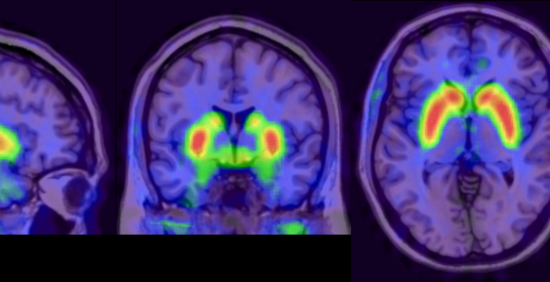

Using neuroimaging to target treatment in psychosis

Neuroimaging